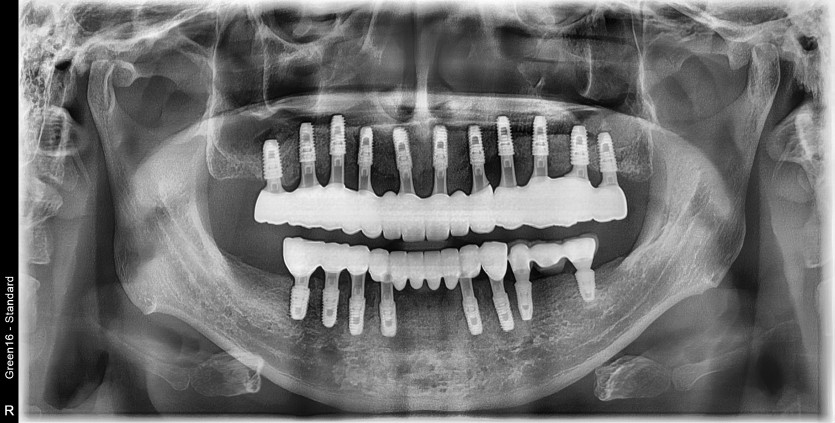

전체 임플란트 증례입니다.

16개의 임플란트로 완성하였습니다.